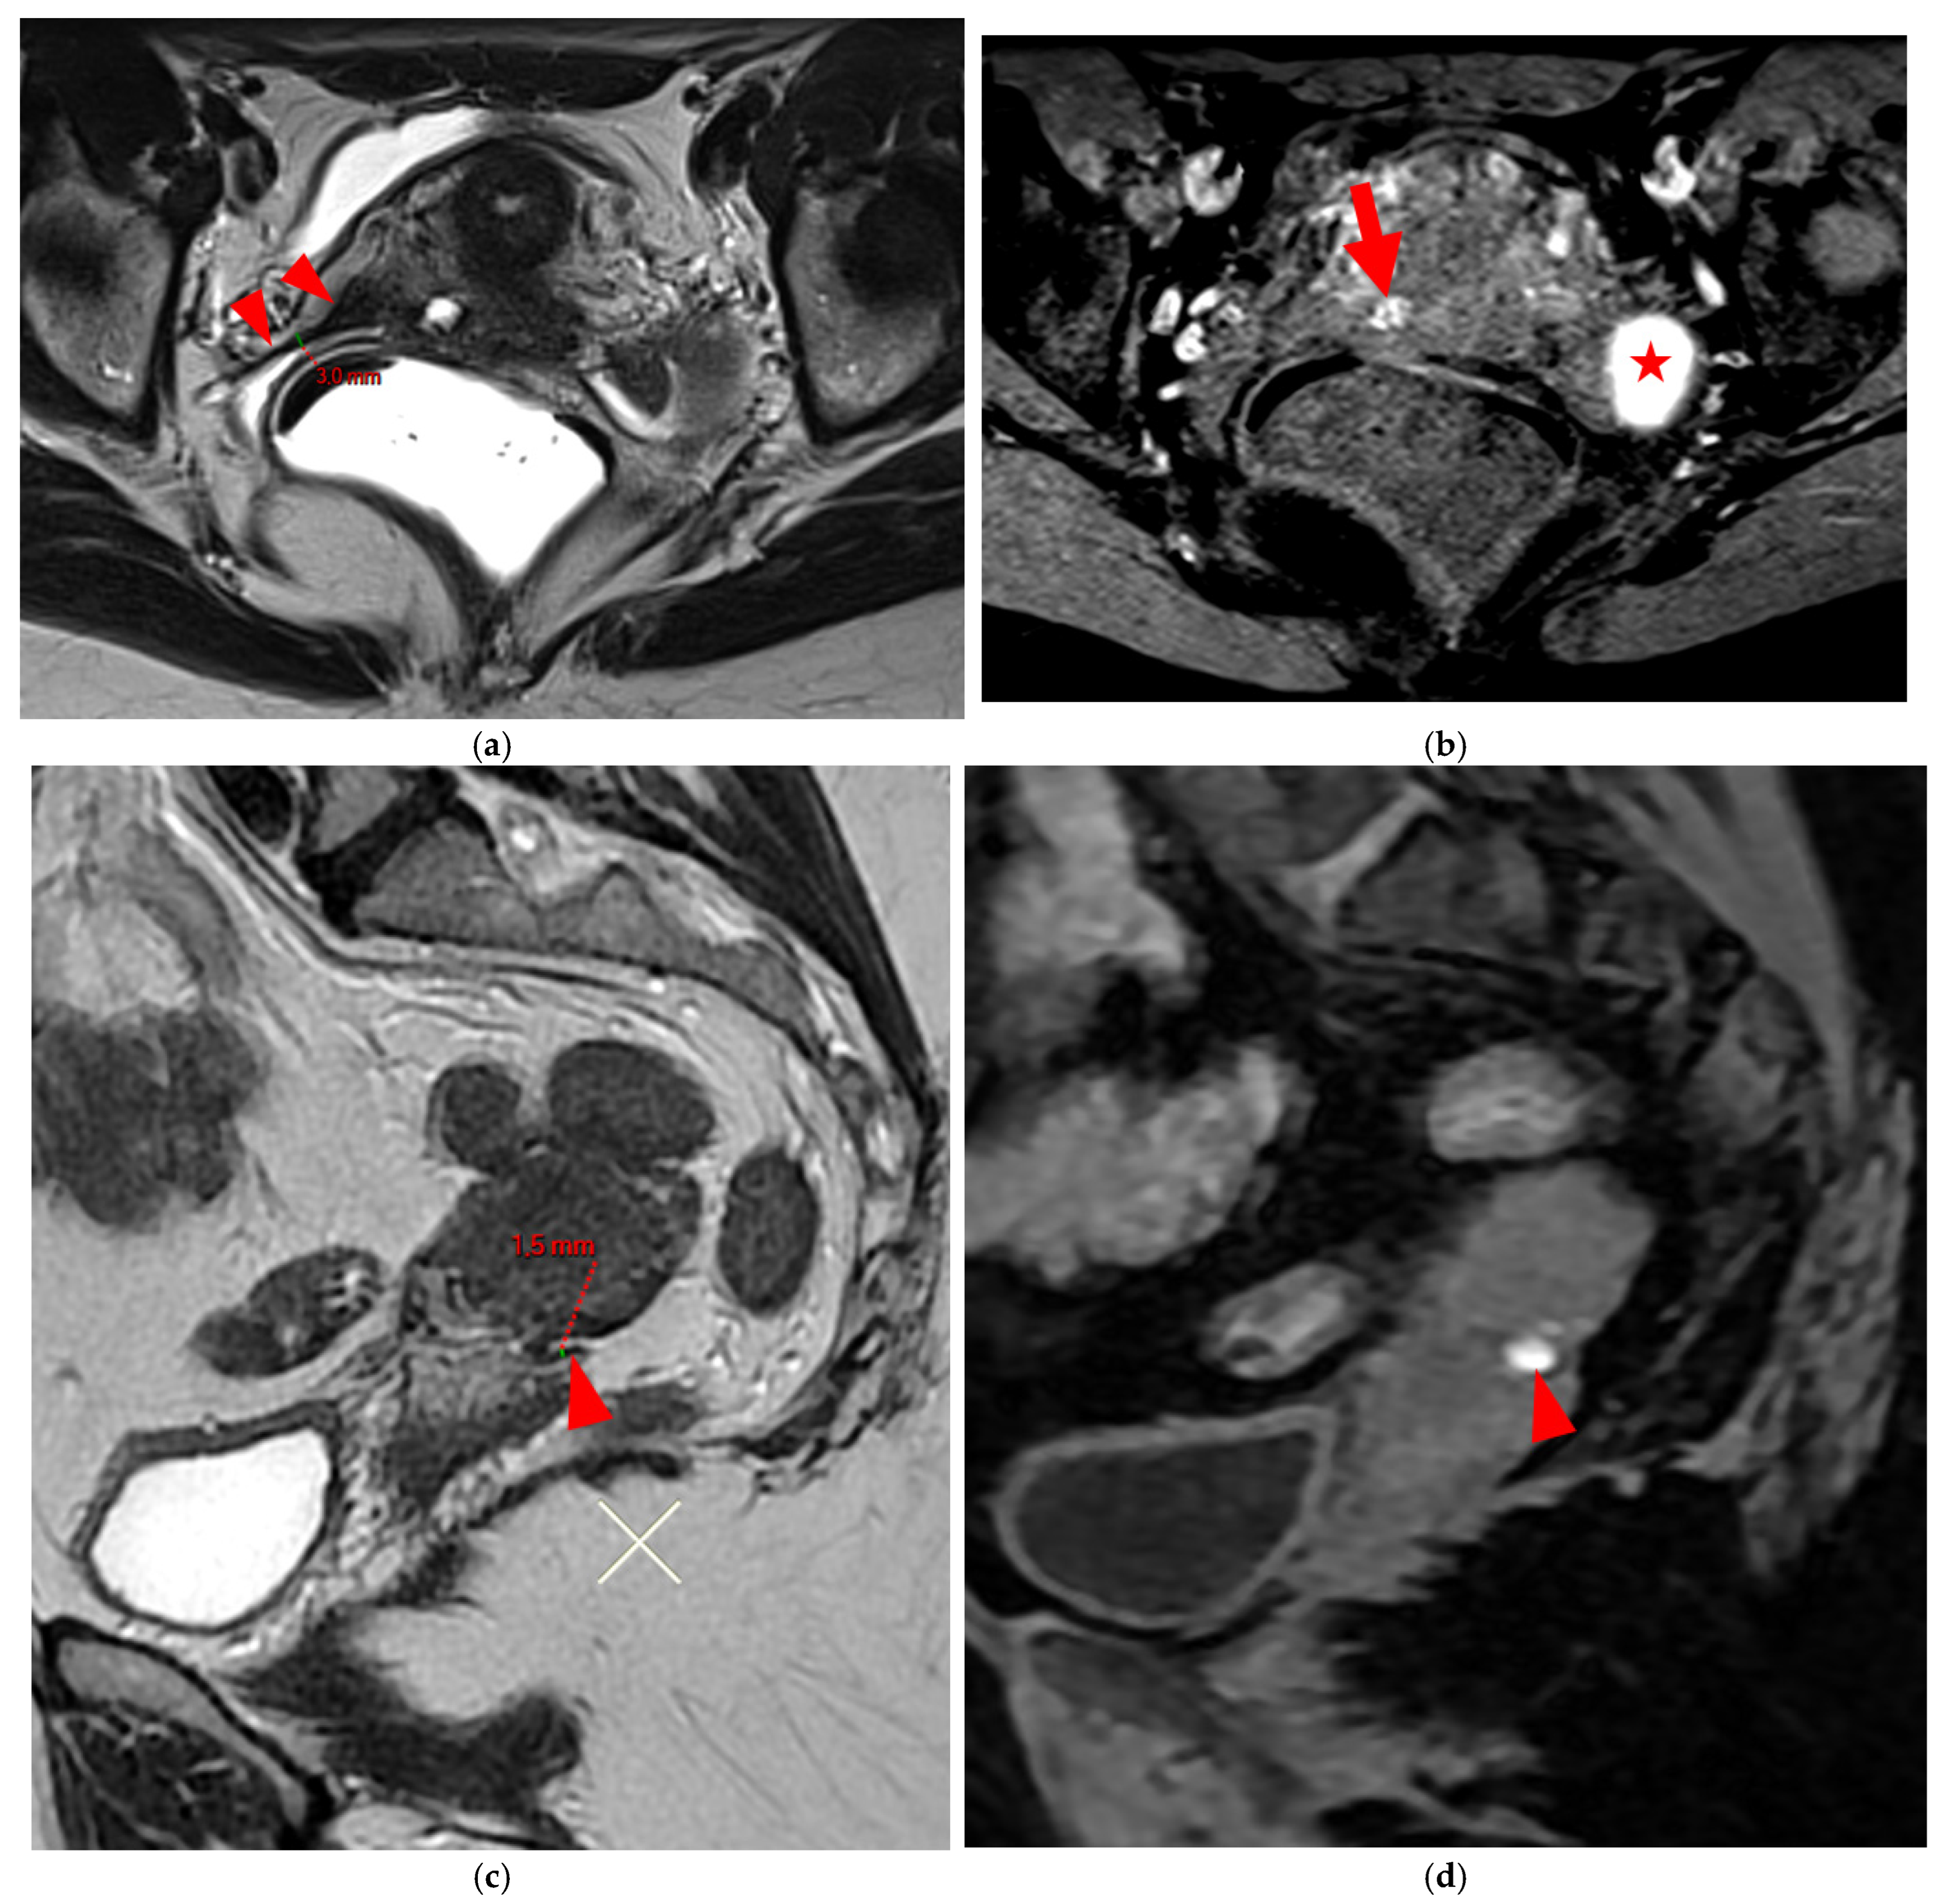

A type 3 USL appears as thickened (i.e., >2 mm), and can be classified either as type 3A (PPV = 75%; FPR = 25%) or as type 3B (PPV = 80%; FPR = 20%).

A type 3A USL (Figure 3) maintains a smooth appearance with regular margins and often retains a tapering shape despite its thickening.

HTD Type 3B USL

A type 3B USL (Figure 4), in addition to being thickened, has a notched surface with slightly irregular margins, or a caliber disparity with focal thickening, or appears “stiffened”, which means it loses its curvilinearity to exhibit a steep vertical orientation in the sagittal plane or a “bowstringing” of the USL in the sagittal or axial planes. Occasionally, a USL might appear thin but “stiffened”, which would upgrade it from a type 2 to a type 3B.

Figure 3. Pelvic MRI scans of three patients with thick (>2 mm), smooth, and regular USLs (HTD type 3A). (a) Sagittal T2WI: a thick (2.8 mm), smooth, tapering-shaped left USL (arrowhead). (b) Axial T2WI: regularly thickened (3 mm) right USL with a smooth surface (arrowhead). (c) Axial T2WI: regularly thickened (4.1 mm) right USL with a smooth surface (arrowheads).

Figure 4. Pelvic MRI scans of seven patients with HTD type 3B USLs. (a) Sagittal T2WI: a thickened (2.1 mm) and stiffened right USL (arrowhead) with “bowstringing”. (b) Axial T2WI: a caliber disparity (dashed arrows) with focal thickening (4.2 mm) of the left proximal USL (arrowhead). (c) Sagittal T2WI: a caliber disparity (dashed arrows) with focal thickening (2.5 mm) of the right distal USL. (d) Axial T2WI: a right USL with a notched and irregular surface (dashed arrows). (e) Axial T2WI: thickened and stiffened left (3 mm) and right (2.5 mm) USLs with “bowstringing” of both USLs (arrowheads). (f) Sagittal T2WI: a thickened (2.6 mm) right USL with a stiffened appearance characterized by a steep vertical orientation (arrowhead). (g) Sagittal T2WI: the right USL appears thin (1.9 mm) but stiffened (arrowhead), exhibiting “bowstringing”. These findings led to its reclassification from type 2 to type 3B.